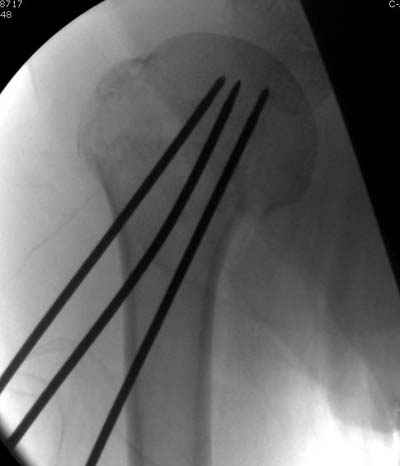

Здесь случай перелома-вывиха плеча, больному 56 лет, после "дважды" закрытой неудачной репозиции, опять же ургентно взяли в операционную, после полного общего обезболивания попытались сделать репозицию, и фиксацию провели спицами.

Больной находился в повязке, примерно напоминяющей косыночную, рекомендованы движения в локтевом суставе и маятниковые движения в плече, спицы удалены в три недели (были случаи миграции)

Больной амбулаторный, предупрежден на случай осложнения АВН головки.